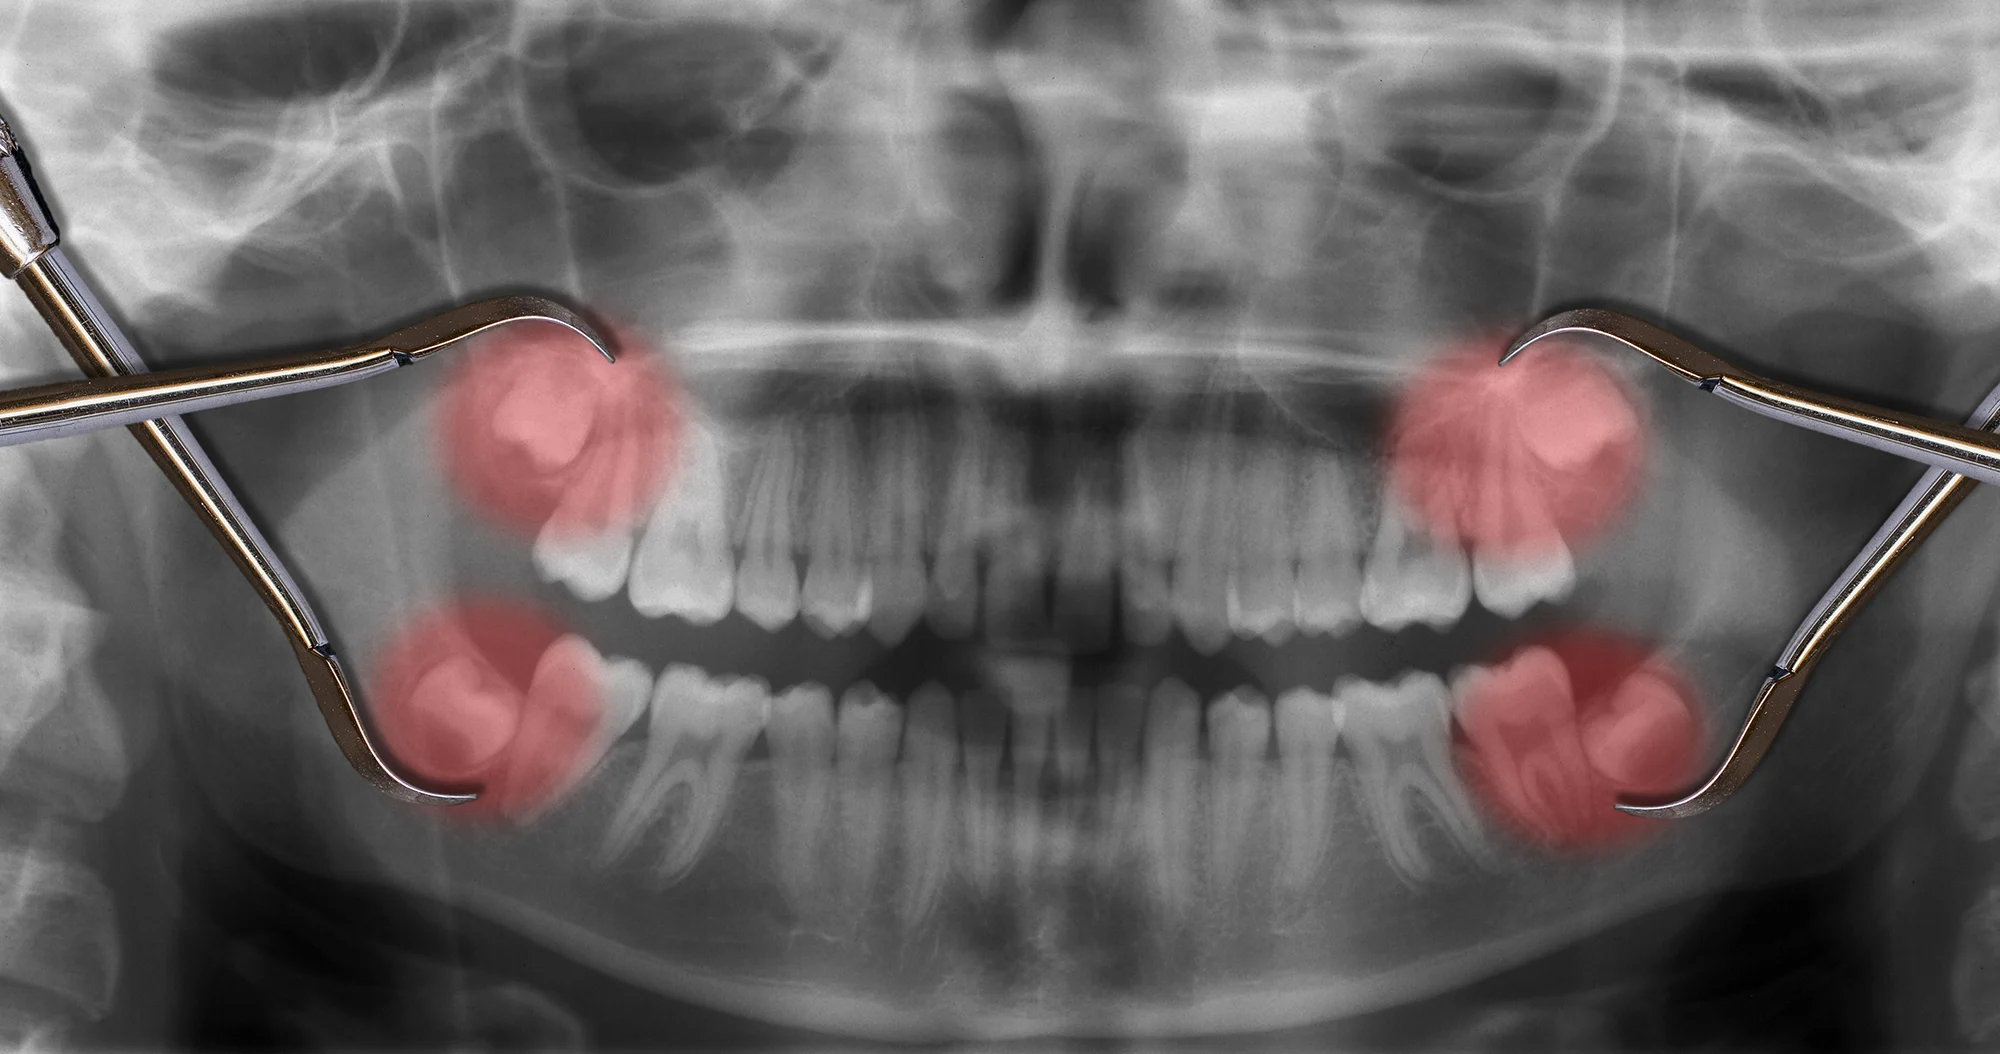

- Denti del giudizio inclusi o problematici.

- Dente incluso o semi-incluso: intervento chirurgico con incisione gengivale e, a volte, rimozione ossea.

- Estrazioni di denti del giudizio, inclusi o parzialmente inclusi.